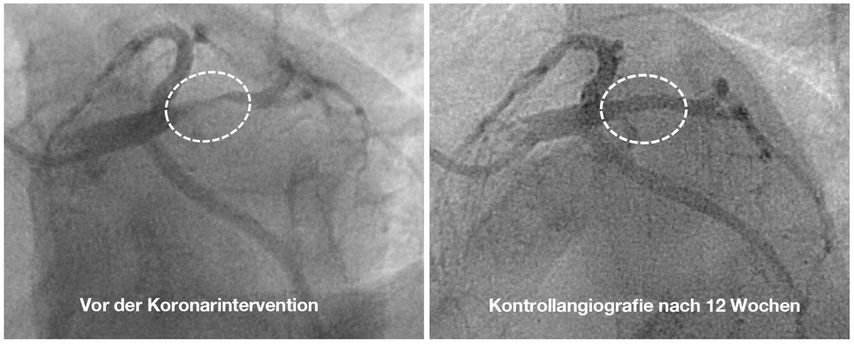

In der Koronarangiografie zeigt sich bei einem 29-jährigen Patienten mit einer positiven Familienanamnese für eine frühe koronare Herzkrankheit und typischer Angina pectoris eine höchstgradige Stenose im grossen Ramus intermedius (Abb. 3, links). Bei diesem jungen Patienten erfolgt die Behandlung mit einem medikamentenbeschichteten Ballon. Die Kontrollangiografie, die aufgrund atypischer Beschwerden durchgeführt wird, zeigt nach 3 Monaten ein gutes Ergebnis ohne residuelle Stenose (Abb. 3, rechts).

Abb. 3: Index-Koronarangiografie mit einer höchstgradigen Intermediäraststenose vor der Behandlung mit einem medikamentenbeschichteten Ballon (links) und Kontrollangiografie nach 12 Wochen ohne residuelle Stenose (rechts)